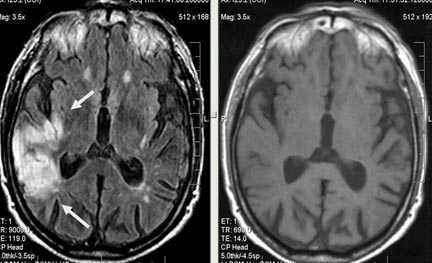

Церебральная гемиатрофия (Dyke-Davidoff-Masson syndrome)

Анамнез: Юноша, 18 лет. Когнитивные нарушения, левосторонний гемипарез с раннего детства. Два эпизода судорог за последние две недели.

Описание исследования Атрофия правого полушария головного мозга с энцефаломаляцией и глиозом в смежных отделах лобной, теменной и височной долей (бассейн правой СМА), exvacuo-дилатация правого бокового желудочка, атрофия ипсилатеральной ножки мозга, базальных ганглиев и таламуса, легкая перекрестная атрофия мозжечка (левая гемисфера), ипсилатеральное смещение срединных структур и некоторое утолщение костей свода черепа.